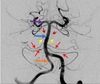

21.2 A 50-year-old man is admitted with a stroke and undergoes cerebral angiography. The artery marked with an ORANGE arrow on the angiogram below is the a) Vertebral b) Basilar c) PICA d) Superior cerebellar e) Anterior cerebral

a) Vertebral orange = vertebral blue = basilar purple = PCA red arrows = AICA yellow = pontine arteries Circle of Willis: